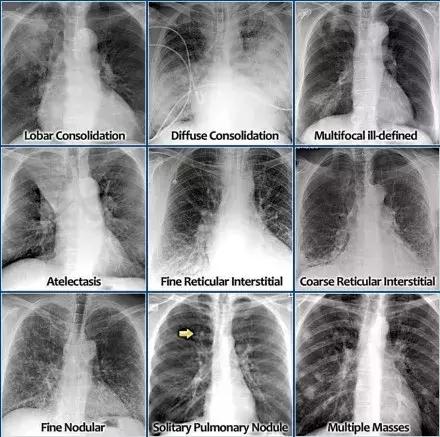

图1 四种分类方式肺部模型

(Consolidation:实变;Interstitial:间质性疾病; Atelectasis:肺不张;Nodules and Masses:结节和团块)

以下9种是四种分类应用举例。

图2 最常见的四种分类方法应用举例

(从左至右。第一行:肺叶实变,弥漫性实变,多发不明确实变病灶。第二行:肺不张,细小网状间质,粗糙的网状间质。第三行:细小结节,孤立性结节,多发性团块)